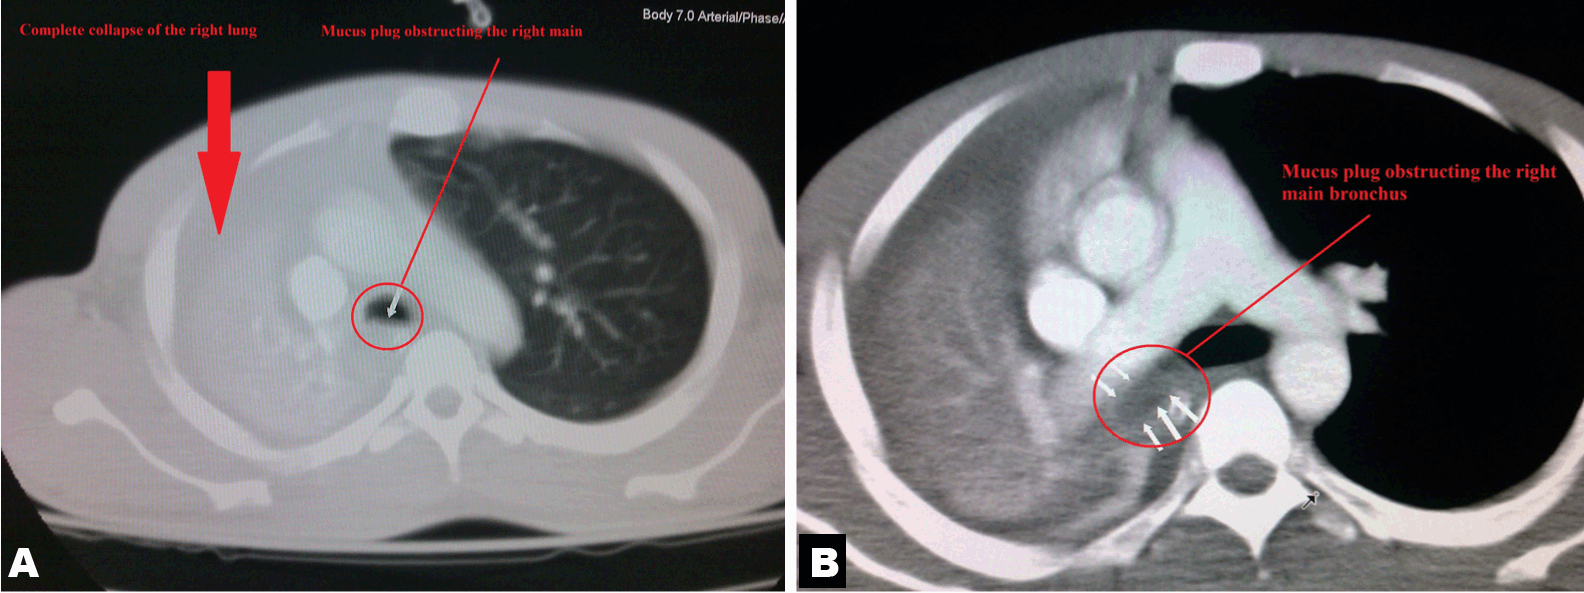

The junior resident who reviewed the chest X-ray felt it was due to a delayed presentation of iatrogenic hemothorax related to the insertion of the central line, and a tube thoracostomy was planned. However, prior to tube thoracostomy, the patient was eventually reviewed by the duty attending trauma surgeon who advised on an emergency computed tomography (CT) scan of the thorax prior to proceeding. The CT scan (Figure 3) revealed a complete collapse of the right lung, with a large mucus plug obstructing the right main bronchus. An emergency awake flexible bronchoscopy was performed (under conscious sedation), and a large amount of mucus was removed using suction. Clinical condition of the patinent improved immediately. A subsequent chest X-ray, six hours after the procedure, showed a complete expansion of the right lung. Following this, his analgesia regime was further escalated, and he was treated with aggressive chest physiotherapy, which was well tolerated. He had an uneventful recovery, did not eventually require a tube thoracostomy, and subsequently discharged on the sixth day.

Cursor on image to zoom/Click text to open image

Figure 3: (A, B) Computed tomoraphy scan of thorax depicting a large mucus plug obstruction of the right main bronchus, with complete collapse of the right lung. Arrow depicting the location of the mucus plug.